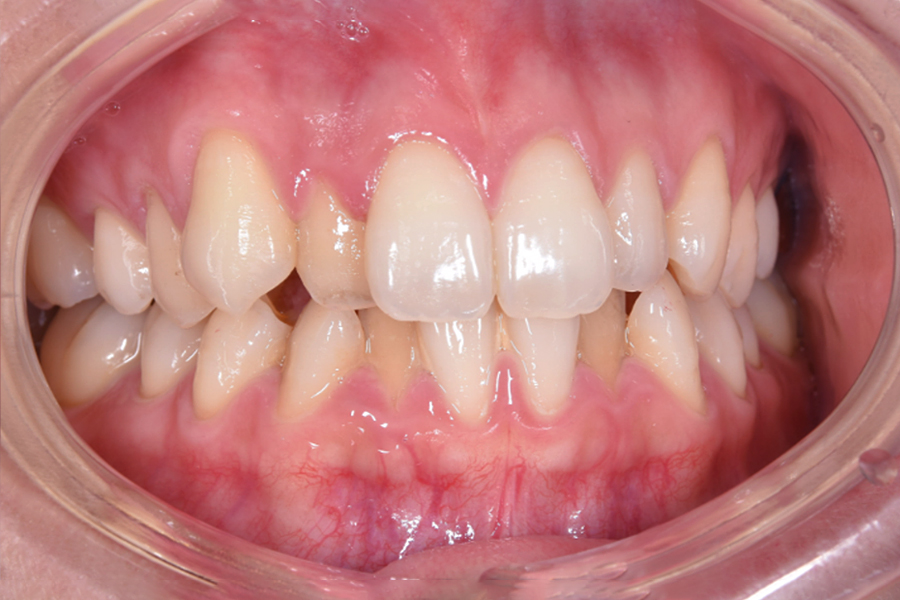

| 主訴 | 前歯で噛めない、 奥歯だけで食事するのが困っている |

|---|---|

| 治療期間 | 3年3か月 |

| 治療費 | ¥980,000(税込) |

| 治療内容 | 目立ちにくいマウスピース矯正(非抜歯矯正) 歯と歯の間に隙間をつくることにより、 歯列弓を広げながら治療を行いました。 |

| 治療のリスク | ・後戻りする可能性があるので リテーナーを最低でも矯正期間以上はつけること ・歯の移動中に、歯の神経が過敏になり冷たいものや熱いものがしみたりする場合があります。 |